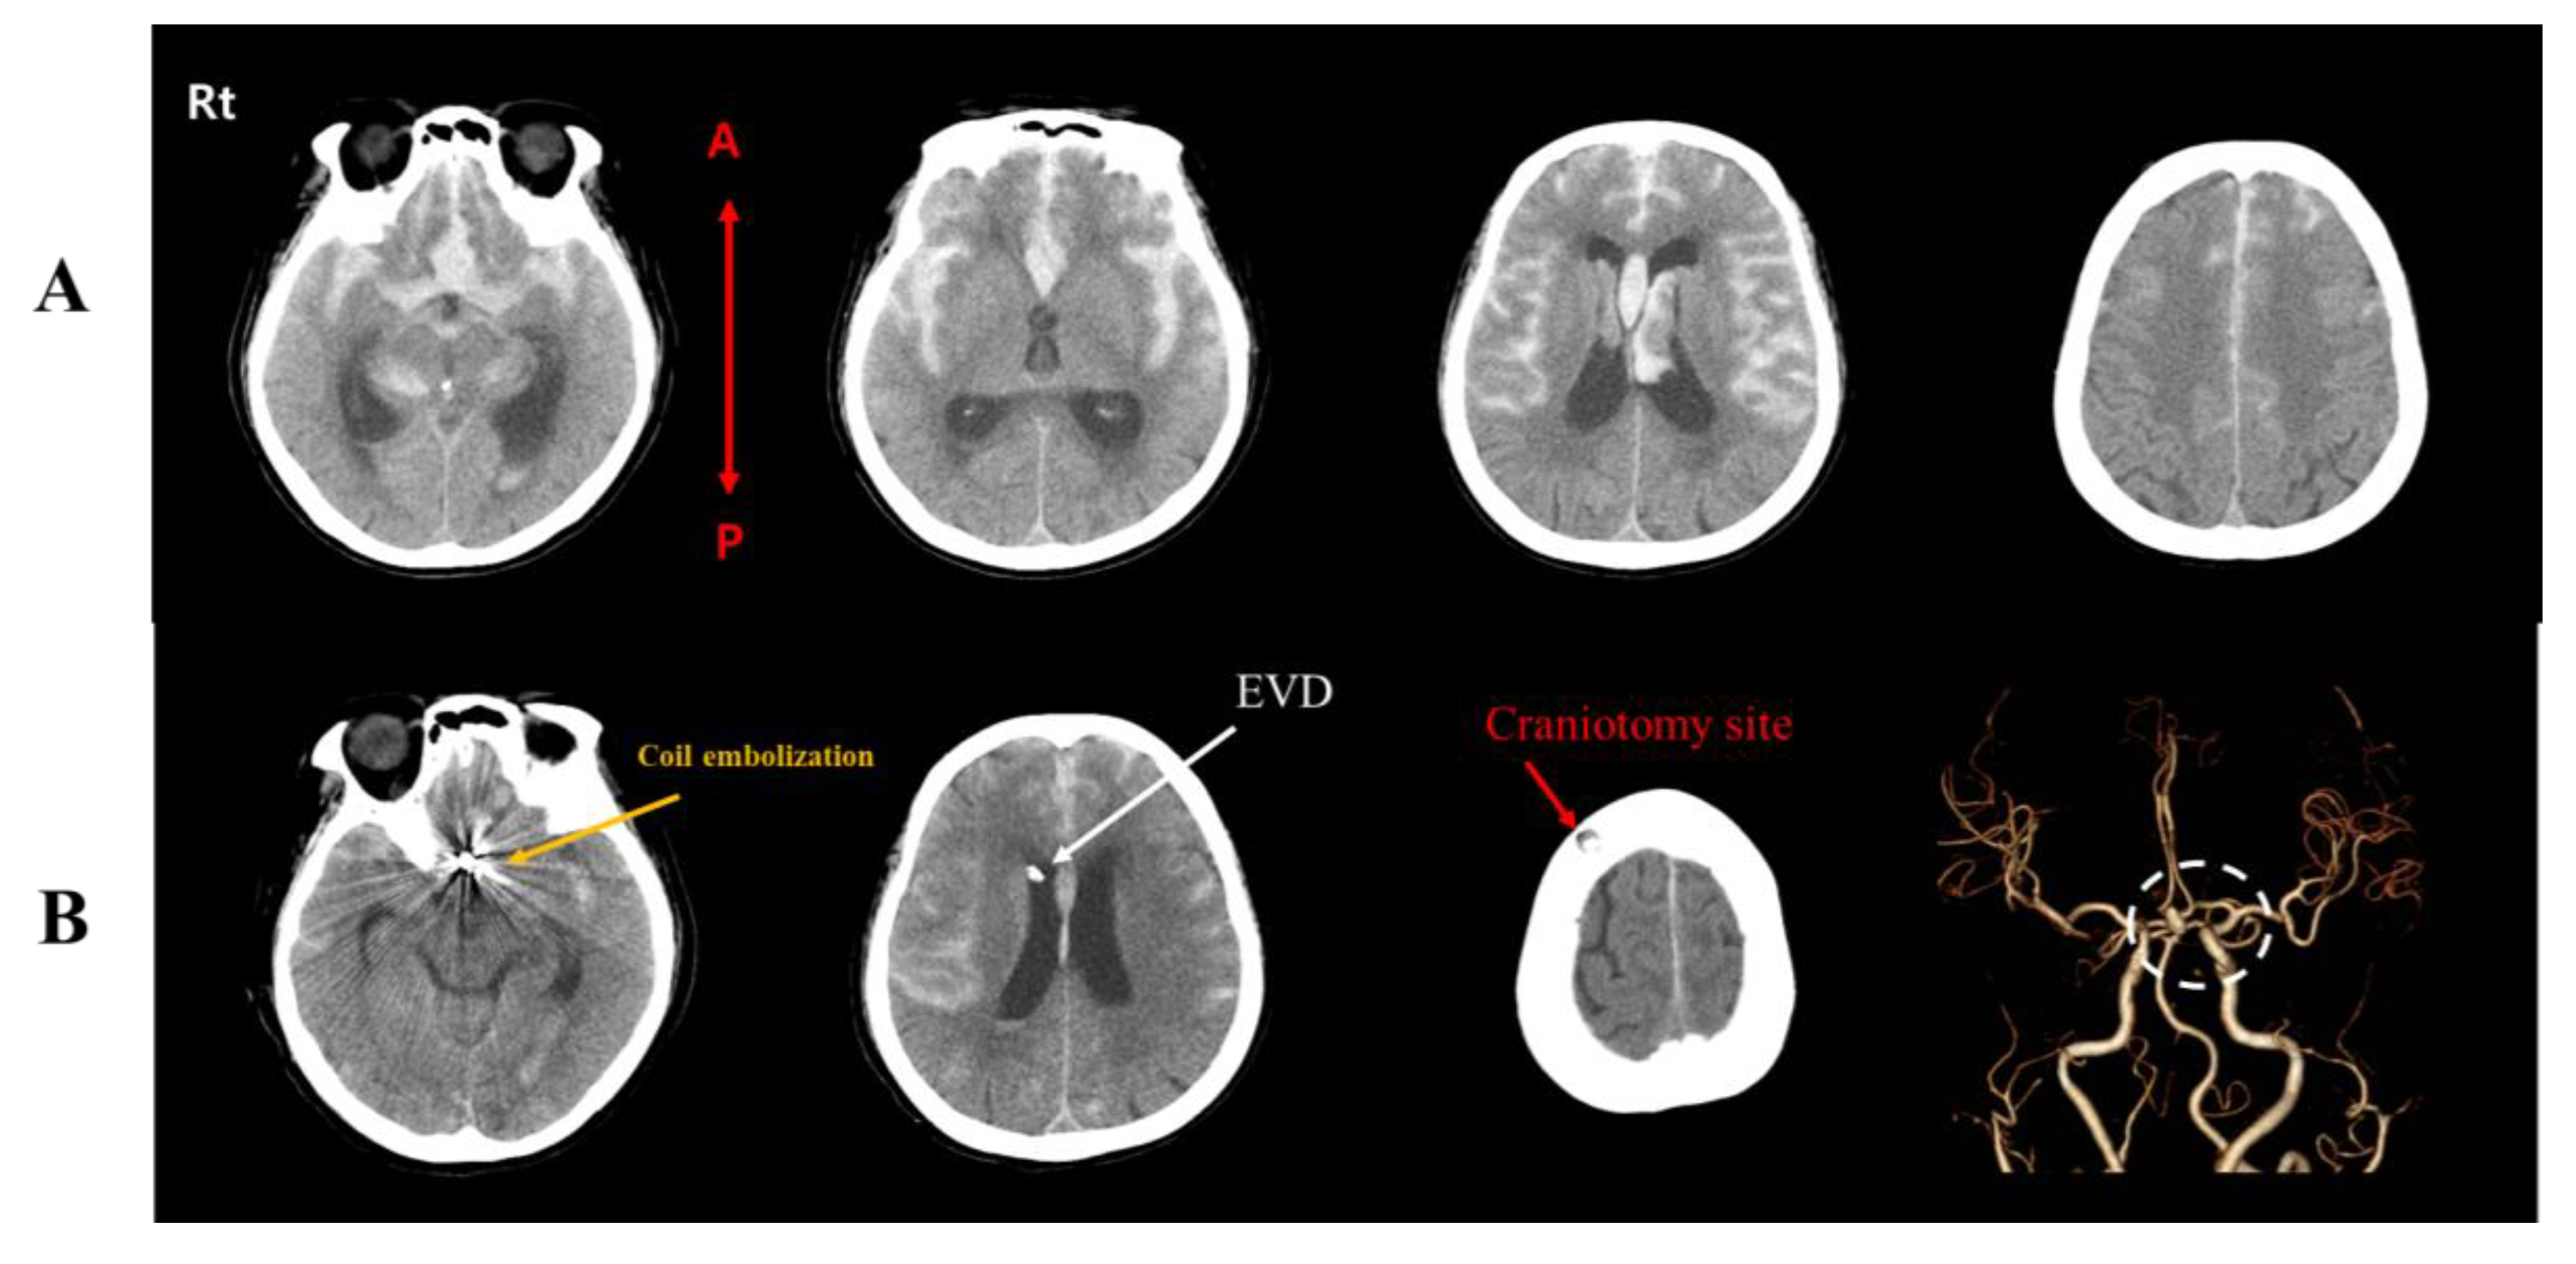

2. Case Presentation